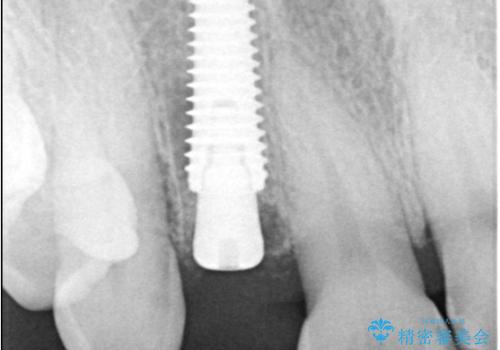

インプラント治療は、低侵襲で短期間に行える「抜歯即時インプラント治療」を選択しました。

この方法は、抜歯したその日にインプラントを埋入し、手術が1回で済むのが大きな特徴です。

治療期間も短く、抜歯からわずか3か月でオールセラミッククラウンを装着することができます。

また、オペ当日には仮歯まで装着するため、見た目を気にせず普段通りの生活を送ることができます。